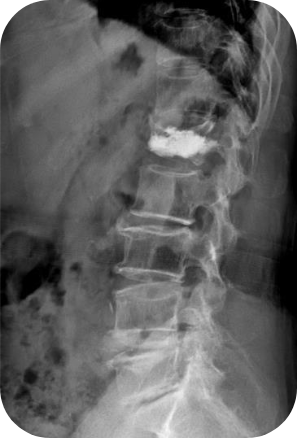

Vertebroplasty

척추체 성형술

척추체 성형술은 골다공증으로 인한 압박골절 때 쓰는 수술법입니다. 골다공증으로 인한 요추 혹은 흉추 골절이 발생하면 참기 힘든 고통이 따릅니다. 너무 아픈 나머지 일어나거나 앉기도 버거운 지경에 이릅니다. 대개 연세가 많은 분들, 특히 여자분들에게 많이 나타납니다. 척추뼈가 심하게 주저 앉은 경우에 척추뼈를 원래 모양으로 회복시킨 후 고정하기 위해 시행하는 수술 방법입니다.

골절은 뼈가 부러진 부위가 움직이면서 통증자극을 유발하게 되는 것인데 이렇게 시멘트를 넣어 단단하게 뼈를 굳히게 되면 통증이 적어집니다. 연세가 극도로 많은 어른분들은 거동이 안되는 상태에서 며칠간 누워 있을 경우 돌이킬 수 없는 합병증이 발생할 수도 있으므로 가급적 빠른 조치가 필요합니다.